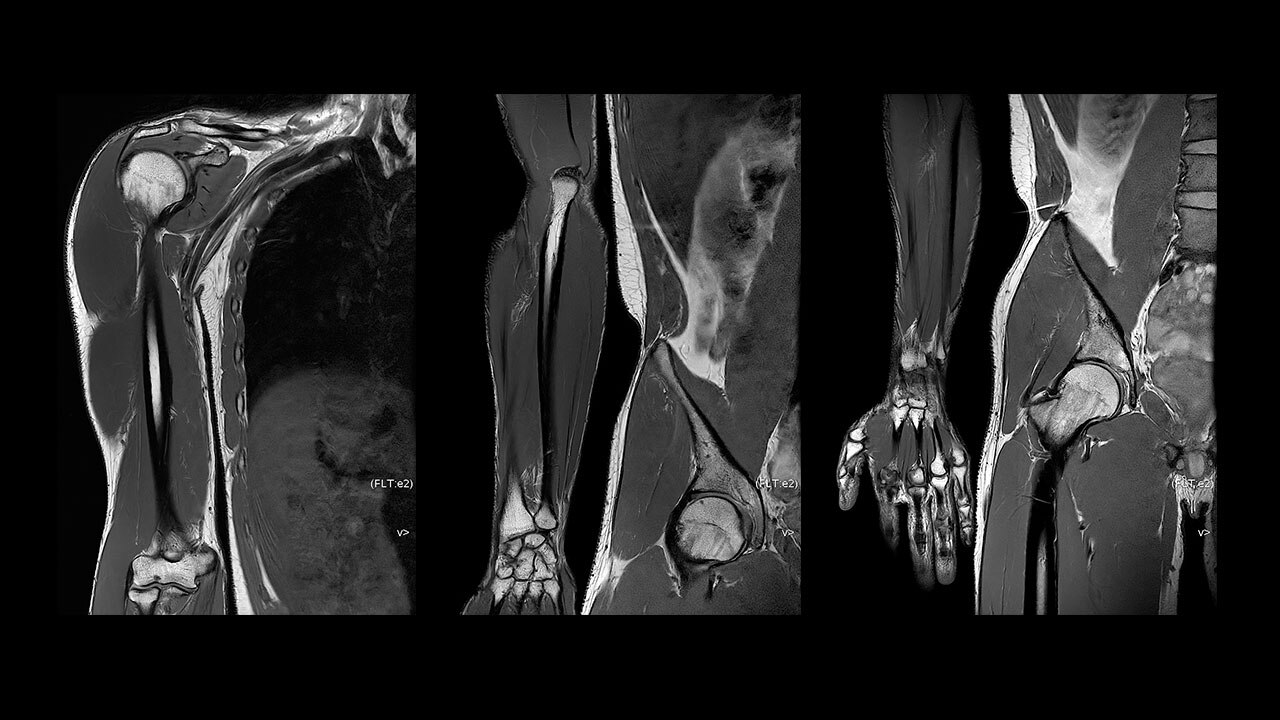

With access to the latest advanced AI technology, you can scan all anatomies and achieve pin-sharp images. Our pioneering Deep Learning-based reconstruction algorithm AIR™ Recon DL accelerates scan time and puts patients at ease.

The improved gradient of up to 80 mT/m,

200 T/m/s provides exceptional results faster and with 146 RF channels, you can ensure uniformity for every result.